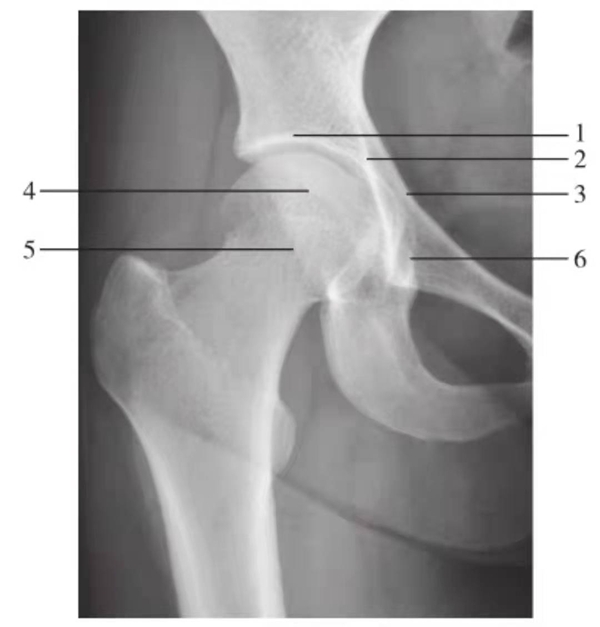

髋关节前后位

图1 髋关节正位片(生长期,9岁)

1.髂骨;2.髋关节间隙;3.Y形软骨;4.股骨头骨骺;5.骨骺板;6.临时钙化带;7.泪滴;8.大转子骨骺;9.股骨颈

图2 髋关节正位片(成人期)

1.髋臼线;2.髂坐线;3.髂耻线;4.前唇线;5.后唇线;6.泪滴